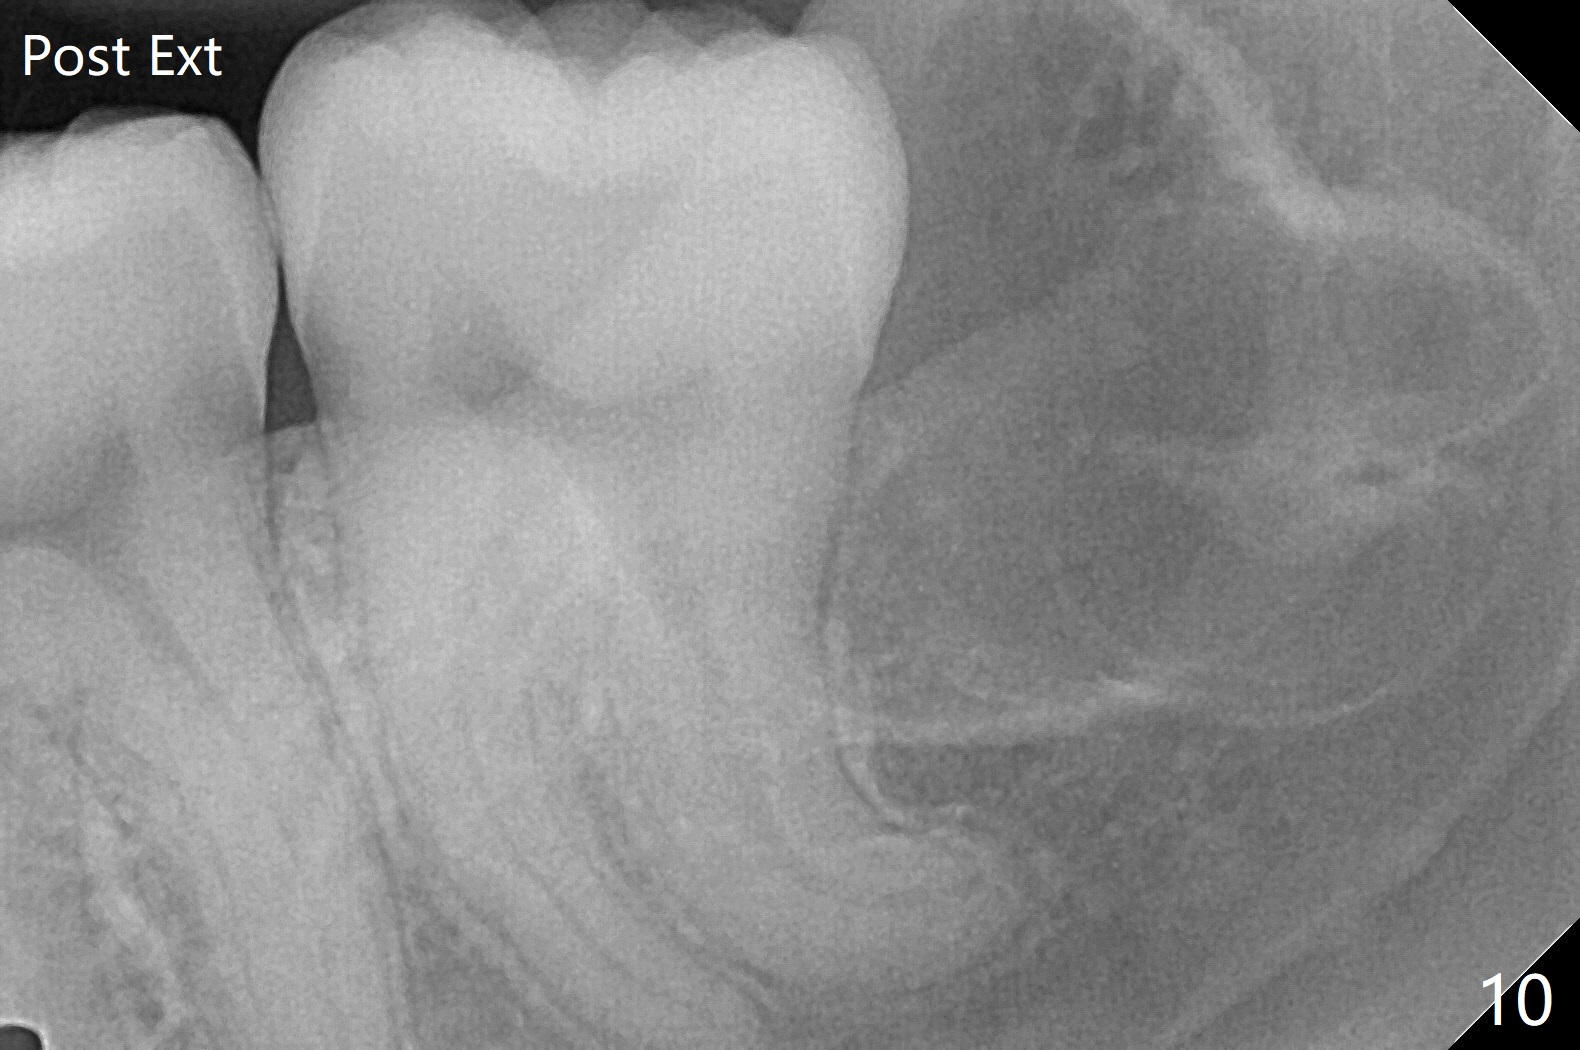

18岁女要求上大学前拔除智齿(图二),十三岁上四已经为了矫正而拔除(图一),所以现在只需要拔除下八,后者接近水平阻生,冠部可能位于下七远中颊侧(图三,四 *),所以附加切口应在七近中(红线)。智齿拔除后根部有两个牙槽窝(图五,六 *)。在右侧,塞入两个胶原塞(图七:1,2,collagen plug),其中一个末端剪开塞入根部牙槽窝。而左侧,使用一个胶原塞,但事先剪成两半(图八:1,3),第一部分也剪成燕尾,插入根部牙槽窝(1),然后在七远中放置骨水泥(1 cc Bond Apatite,2 红色),在后者上面放入胶原塞另外一半(3)。最后两侧都使用4-0 PGA 缝线。

使用胶原塞目的是预防干槽症,以前病例显示它促进骨化中心形成。骨水泥是一种医用性石膏(Biphasic Calcium Sulphate 硫酸钙 ),容易被身体吸收,3个月转换成自体骨。她哥哥(19岁)病例显示骨水泥与Osteogen Plug同样五个月会形成骨质。以后年轻人(25岁以下)智齿拔除不必植骨或者放置骨水泥。左下,右下智齿的确位于第二磨牙颊侧,事先附加切口近中,缝合后伤口不易裂开,骨粉丢失。拔除后即刻拍摄根尖片(图九,十),目的建立原有解剖,与愈合后比较,意外发现断裂牙片(F),后来取出。